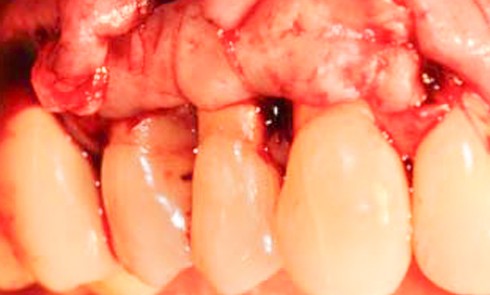

Face aux récessions de classe 1 de Cairo [1] et en présence d’un vestibule relativement profond, une technique de recouvrement radiculaire par lambeau positionné coronairement selon Zucchelli et De Sanctis [2] associé à un greffon conjonctif est choisie.

Cette technique permet de recouvrir des récessions gingivales contiguës par une traction coronaire après une dissection partielle superficielle au-delà de la ligne muco-gingivale. Grâce à un jeu d’incisions des papilles, les incisions de décharge ne sont pas nécessaires. Un greffon conjonctif prélevé au palais selon la technique de l’enveloppe [3] est placé sur les récessions et suturé en même temps que le lambeau par des points suspendus [4].

Dans notre cas clinique, l’intervention a duré un peu moins d’une heure.